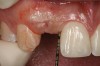

Figure 4  Characterization of the interproximal bone and tooth contacts: A periapical radiograph assists in measuring the distance from bone crest to the adjacent tooth contact points for missing tooth No. 8. The mesial bone crest to the adjacent tooth contact distance is < 5 mm, while the distal bone crest to adjacent tooth contact distance is > 6 mm (Fig 4). One-year following implant placement, conservation of these dimensions is revealed (Fig 5). The clinical photograph (Fig 6) of the lateral incisor adjacent to tooth No. 8 implant crown demonstrates that the absence of distal interproximal (papilla) fill related to the observed bone crest to contact distance exceeds 6 mm.

Figure 4

Figure 5  Characterization of the interproximal bone and tooth contacts: A periapical radiograph assists in measuring the distance from bone crest to the adjacent tooth contact points for missing tooth No. 8. The mesial bone crest to the adjacent tooth contact distance is < 5 mm, while the distal bone crest to adjacent tooth contact distance is > 6 mm (Fig 4). One-year following implant placement, conservation of these dimensions is revealed (Fig 5). The clinical photograph (Fig 6) of the lateral incisor adjacent to tooth No. 8 implant crown demonstrates that the absence of distal interproximal (papilla) fill related to the observed bone crest to contact distance exceeds 6 mm.

Figure 5

Figure 6  Characterization of the interproximal bone and tooth contacts: A periapical radiograph assists in measuring the distance from bone crest to the adjacent tooth contact points for missing tooth No. 8. The mesial bone crest to the adjacent tooth contact distance is < 5 mm, while the distal bone crest to adjacent tooth contact distance is > 6 mm (Fig 4). One-year following implant placement, conservation of these dimensions is revealed (Fig 5). The clinical photograph (Fig 6) of the lateral incisor adjacent to tooth No. 8 implant crown demonstrates that the absence of distal interproximal (papilla) fill related to the observed bone crest to contact distance exceeds 6 mm.

Figure 6